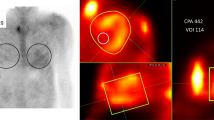

Table 2 and Figure 2 summarize the uptake parameters in images of all 23 patients acquired 1 hour after 99mTc-PYP injection. The volumetric parameters CPV and CPA decreased as thresholds increased. The myocardial SUVmax/aortic blood pool SUVmax and myocardial SUVmax/vertebral SUVmax were 2.1 ± .7 and 1.5 ± .7, respectively. In a patient with low abnormal myocardial uptake, we evaluated SUVmax in the interventricular septum on fused SPECT/CT images.

Comparison of SUVmax (A) and SUVmax ratios (B) at 1 h after 99mTc-PYP injection (n = 23). Green and blue lines indicate means and standard deviations, respectively. Box plot indicates medians, 25%, and 75% quartiles with whiskers at both ends. Retention index = (myocardial SUVmax/vertebral SUVmax) × paraspinal muscle SUVmax. 99mTc-PYP, Technetium-99m pyrophosphate; SUV, standardized uptake value